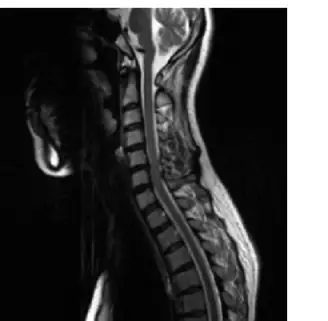

依據下圖之影像,下列敘述何者正確?

AT-spine sagittal view FSE-T1 weighted

BC-spine sagittal view FSE-T1 weighted with contrast enhancement

CC-spine sagittal view FSE-T2 weighted

DL-spine sagittal view FSE-T1 weighted

影像呈現矢狀切面脊椎 MRI,觀察重點如下:

掃描部位判斷:影像上方可見頭骨底部(顱底)及腦幹,椎體呈頸椎特有的前凸弧度,共可辨識約 7 節椎體,符合頸椎(cervical spine, C-spine)的解剖範圍。胸椎偏長且弧度向後凸,腰椎椎體較粗大,均不符。

加權序列判斷(T1 vs T2):

- 脊髓周圍腦脊髓液(CSF)呈明顯高訊號(亮白色):此為 T2 加權的核心特徵。T2 加權中,含水量高的組織(CSF、椎間盤髓核)呈高訊號(bright);T1 加權中,CSF 呈低訊號(dark)。

- 椎間盤呈相對高訊號:正常含水椎間盤在 T2 影像中呈亮訊號,符合 T2 加權特徵。

- 脊髓本身呈中等偏低訊號,與周圍高訊號 CSF 形成清晰對比,此為 T2 myelogram-like 效果。

- 影像中無對比劑強化的整體增亮現象,排除 contrast enhancement 的可能。